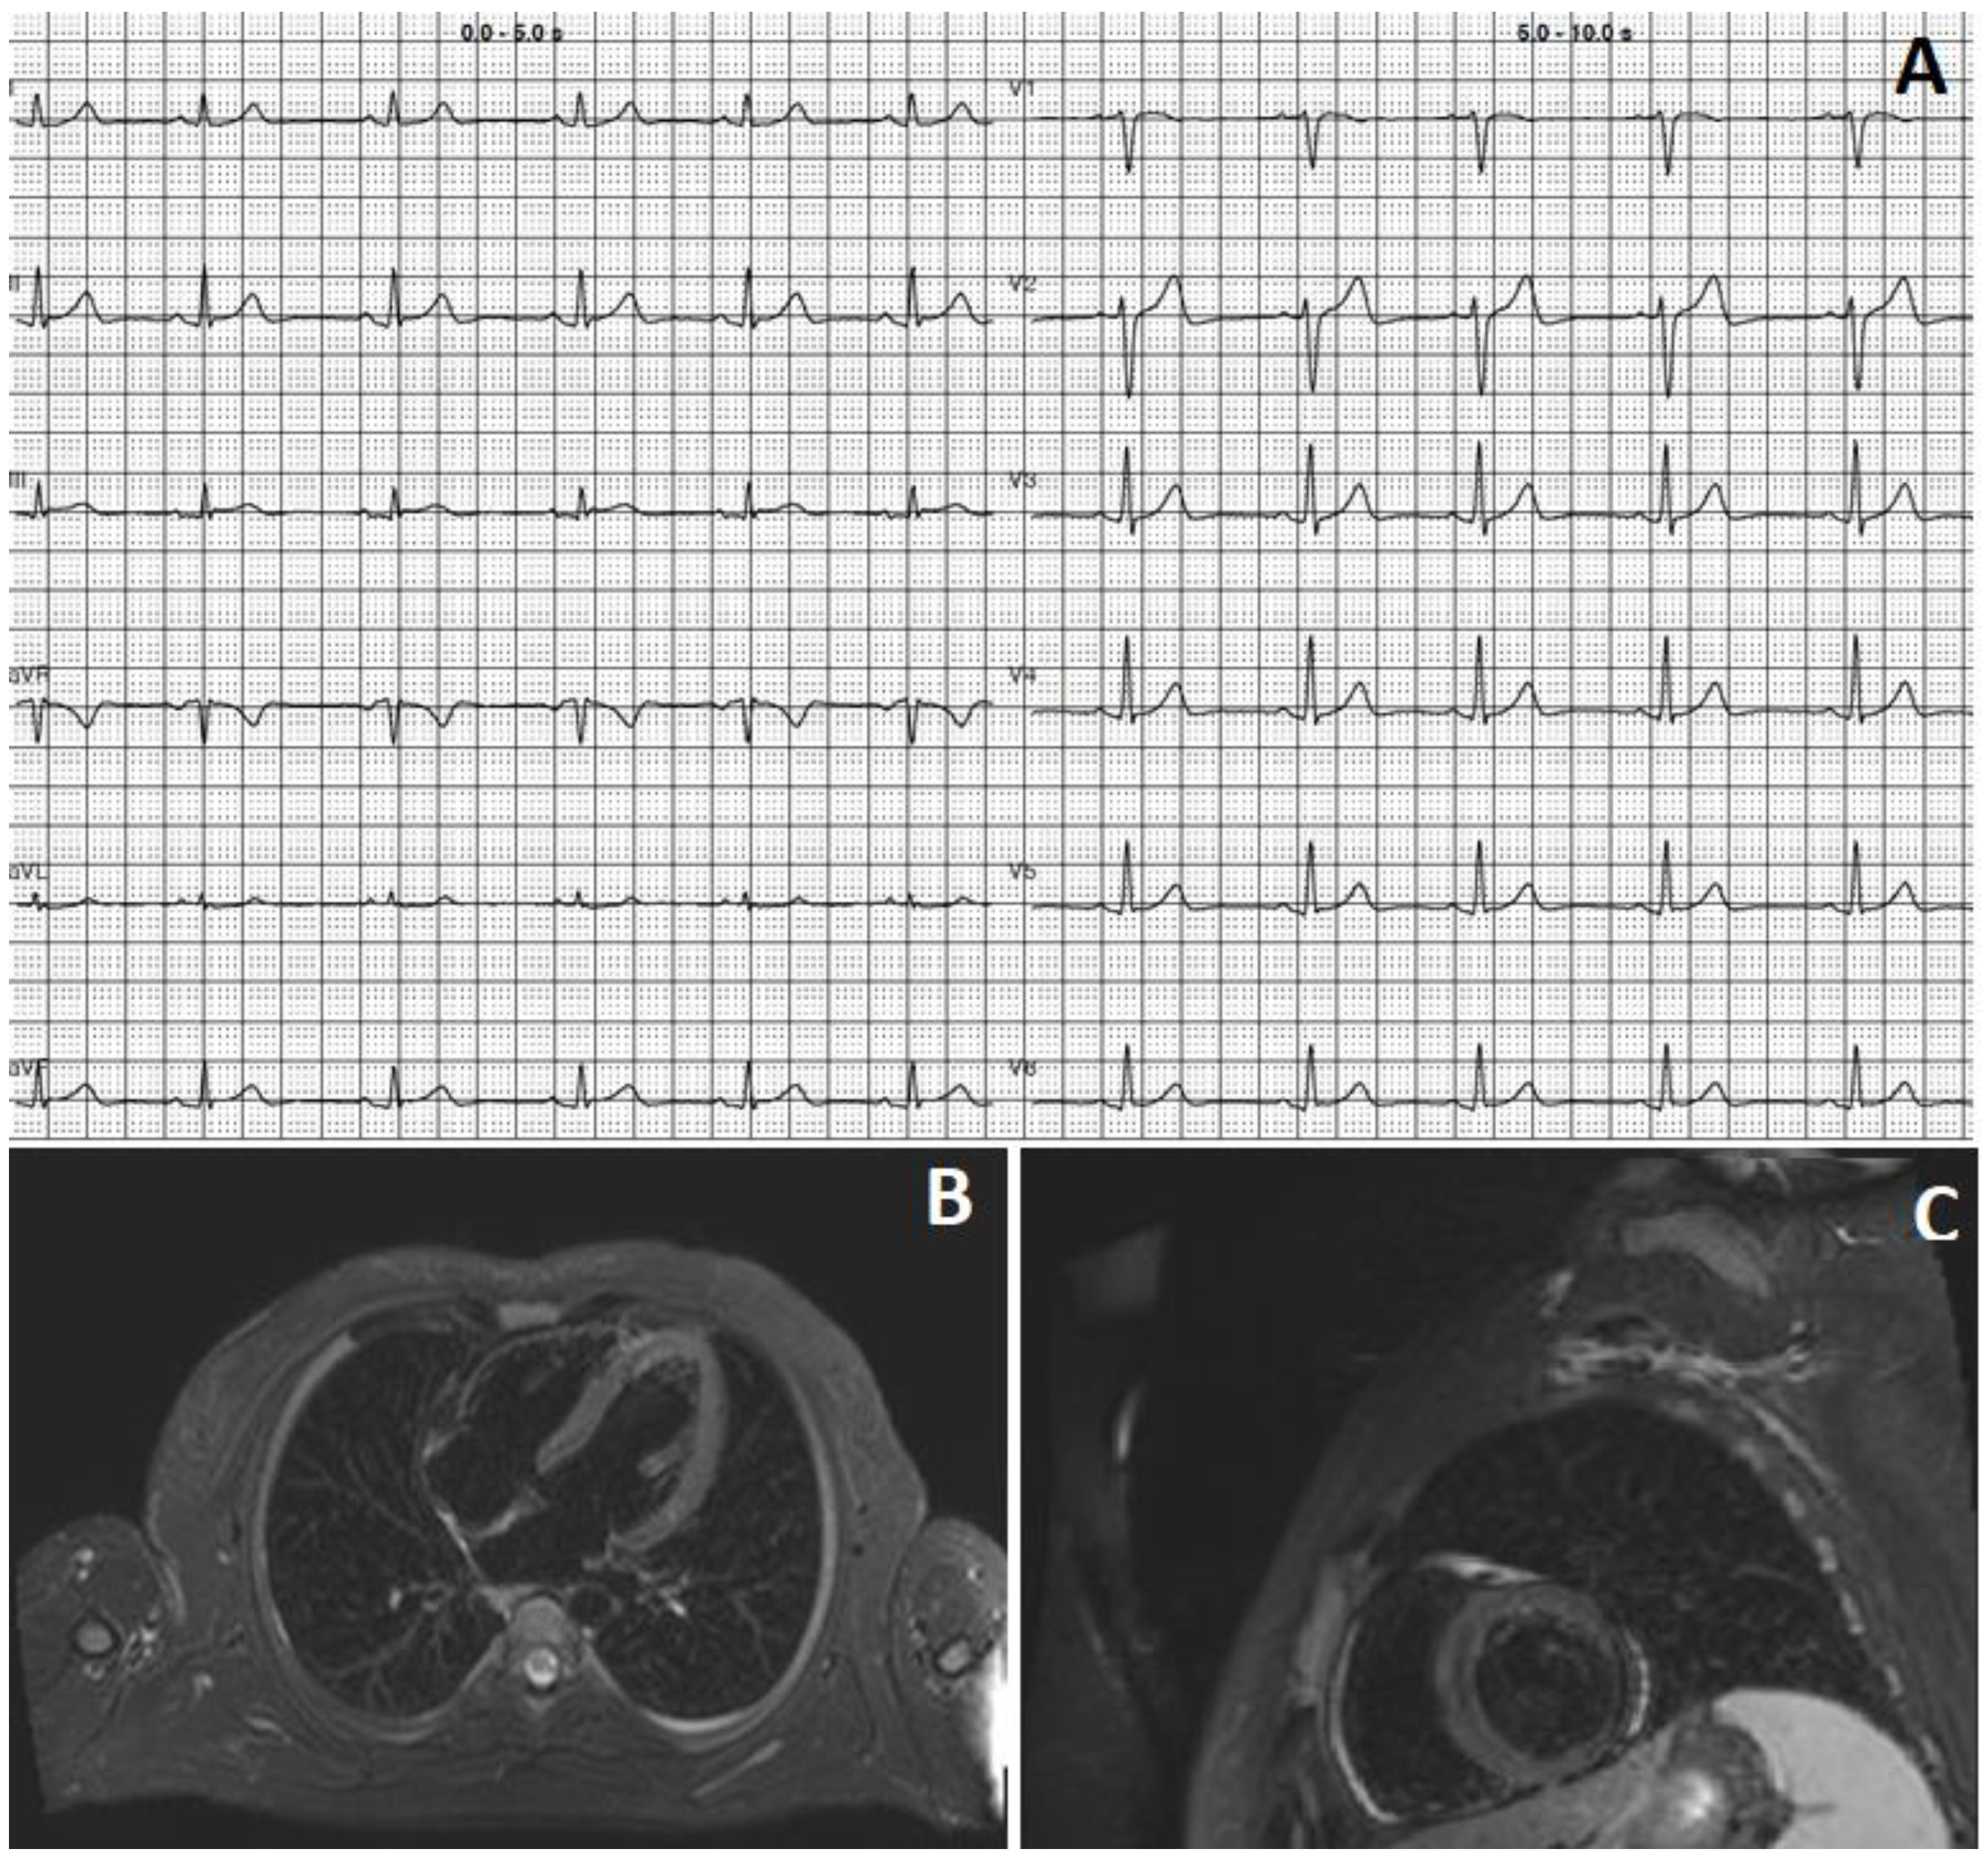

2. Case 1

3. Case 2